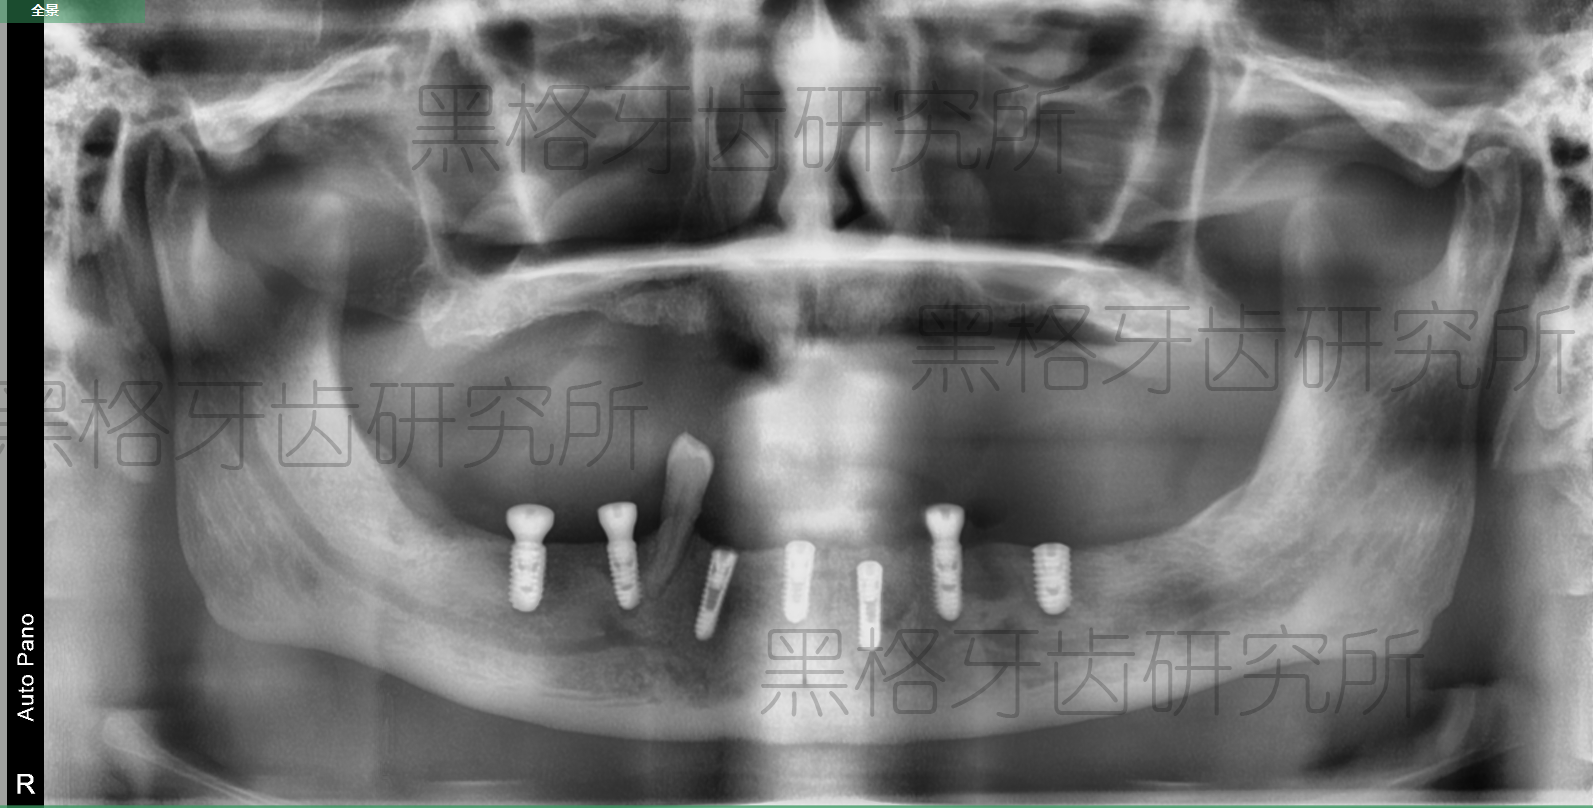

梁阿伯種植后牙片展示

手術(shù)開始后,院方使用了黑格科技提供的種植方案和種植導(dǎo)板,在不到一個小時的時間里,就順利完成了7顆種植體的種植,整個過程對牙齦和牙槽骨的傷害極小,麻藥過后梁阿伯也沒有感受到多少疼痛或不適。

因?yàn)榛旧鲜菍儆谌谌笔?,所以醫(yī)院準(zhǔn)備讓梁阿伯做兩次手術(shù),第一次種植下頜牙列,第二次種植上頜牙列。在方案選擇上,醫(yī)生根據(jù)梁阿伯的牙槽骨情況,終選擇種植7顆種植體,并在電腦上向梁阿伯展示了方案。